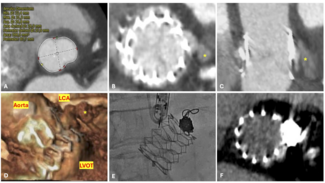

We could not wire antegradely into the mid RCA in spite of using multiple wires, as there was an acute bend at the origin of the acute marginal branch. We eventually used a "hairpin wire" technique, in which a Whisper wire (Abbott Vascular) was bent approximately 3 cm from its tip, advanced into the acute marginal branch, and pulled back (Figures 1D and 1E). We then attempted to advance a balloon into the distal RCA, but were not successful and in the process, the guidewire and guide catheter position were lost.

We engaged the RCA again with an 8 Fr JR4 guide and rewired into the acute marginal branch distal to the CTO and into the distal RCA using the same "hairpin wire" technique. We once again encountered significant difficulty delivering equipment to the distal RCA. Several 1.5 mm balloons could not cross. We were finally able to advance a Corsair catheter (Asahi Intecc) (arrow, Figure 2B) to the distal RCA using an anchor balloon technique with a 2.5 mm balloon into a small proximal RCA conus branch (arrowhead, Figure 2B). The Whisper wire (Abbott Vascular) was exchanged for an Ironman wire (Abbott Vascular, arrowhead, Figure 2C), which enabled sequential delivery of 2.0, 2.5, and 3.0 mm balloons and predilation of the entire proximal, mid, and distal RCA. We were then able to deliver three 3.0 mm x 28 mm Xience V everolimus-eluting stents (Abbott Vascular) using a Guideliner catheter (Vascular Solutions, arrow, Figure 2C) for extra guide support. The stents were postdilated with a 3.5 mm non-compliant balloon, providing an excellent final angiographic result (Figure 2D), as confirmed by intravascular ultrasonography. The total fluoroscopy time and air kerma radiation dose were 39.2 minutes and 7.4 Gray, respectively, and 358 mL of contrast were administered. At 1-month follow-up the patient was angina-free and had significantly increased his daily activities.

We engaged the RCA again with an 8 Fr JR4 guide and rewired into the acute marginal branch distal to the CTO and into the distal RCA using the same "hairpin wire" technique. We once again encountered significant difficulty delivering equipment to the distal RCA. Several 1.5 mm balloons could not cross. We were finally able to advance a Corsair catheter (Asahi Intecc) (arrow, Figure 2B) to the distal RCA using an anchor balloon technique with a 2.5 mm balloon into a small proximal RCA conus branch (arrowhead, Figure 2B). The Whisper wire (Abbott Vascular) was exchanged for an Ironman wire (Abbott Vascular, arrowhead, Figure 2C), which enabled sequential delivery of 2.0, 2.5, and 3.0 mm balloons and predilation of the entire proximal, mid, and distal RCA. We were then able to deliver three 3.0 mm x 28 mm Xience V everolimus-eluting stents (Abbott Vascular) using a Guideliner catheter (Vascular Solutions, arrow, Figure 2C) for extra guide support. The stents were postdilated with a 3.5 mm non-compliant balloon, providing an excellent final angiographic result (Figure 2D), as confirmed by intravascular ultrasonography. The total fluoroscopy time and air kerma radiation dose were 39.2 minutes and 7.4 Gray, respectively, and 358 mL of contrast were administered. At 1-month follow-up the patient was angina-free and had significantly increased his daily activities.